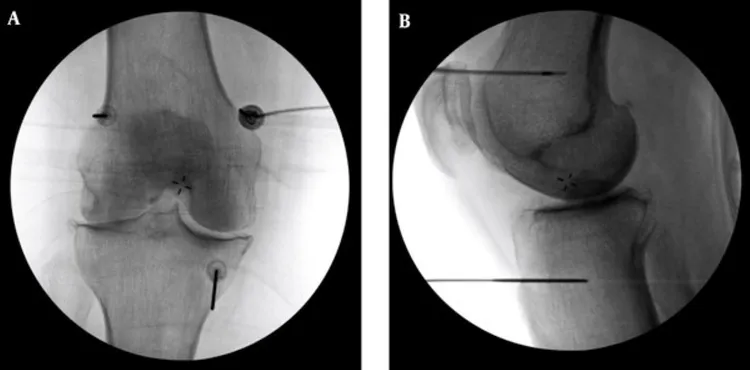

高頻熱凝療法以X光定位將電極導針導引至膝蓋的三個主要感覺神經叢,藉由熱能與電效應,麻痺痛覺神經。台北慈濟提供